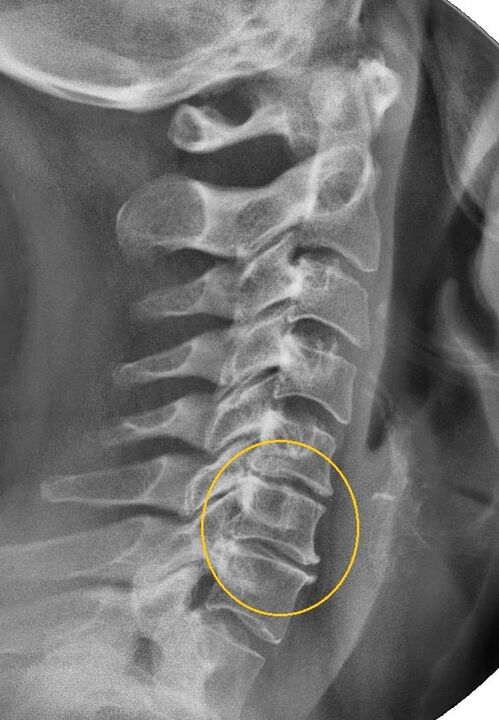

The most informative diagnostic procedure is radiography.Grade 1 pathologies correspond to radiological stage 1 or 2.The obtained images visualize the typical signs of the disease.

| X-ray stages of cervical osteochondrosis of the 1st degree | Characteristic signs |

|---|---|

| Phase 1 | Minor changes in the curvature of the spine in the cervical region affecting one or more segments |

| Phase 2 | Slight thickening of the intervertebral discs, deformation of the uncinate appendages, correction of lordosis, minor growths of bony structures |